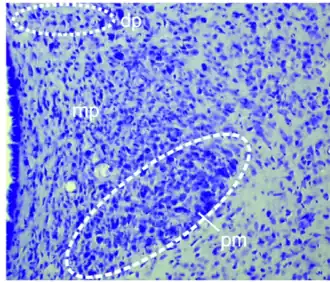

La región parvocelular del PVN, según la densidad celular y el tamaño celular, muestra las subdivisiones anterior (ParaventricularAnteriorParvo, PaAP), medial (PaMP), posterior (PaPo) y periventricular (Pe).

La región magnocelular del PVN se caracteriza por la agrupación compacta de células grandes y tiene subdivisiones lateral (ParaventricularLateralMagno PaLM) y medial (PaMM).[4]

Las dos poblaciones principales reciben el nombre de área parvocelular y área magnocelular.[7]

Parvocelulares (dp, mp) arriba.

- La región magnocelular contiene grandes células que producen hormona antidiurética y oxitocina. Ambas se sintetizan en forma de prohormonas en el núcleo paraventricular y por vía axonal alcanzan la neurohipófisis donde son almacenadas en gránulos hasta que se produce la secreción a la sangre mediante un proceso de exocitosis. La producción de hormona antidiurética no es exclusiva del núcleo paraventricular, se sintetiza también en el núcleo supraóptico del hipotálamo.

- La región parvocelular contiene neuronas más pequeñas, que liberan una hormona peptídica, denominada "factor liberador", "factor hipófisotrópico" y actualmente hormona liberadora (Releasing Hormone (RH)). Estas neurohormonas son secretadas en el plexo capilar del sistema porta de la Eminencia media (ME), desde donde viajan hasta la Adenohipófisis para estimular la secreción de la hormona. Este tipo de células pequeñas son las que producen: hormona liberadora de hormona adrenocorticotropa (CRH o ACTHRH) y las que secretan la hormona liberadora de tirotropina (TRH o TSHRH).[3][8]